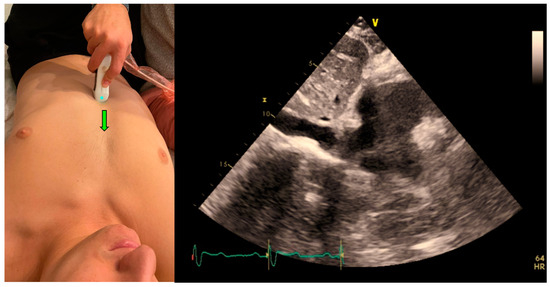

5. VTI Measurement

An expert POCUS operator acquired the views by placing the probe horizontally in the apex of the heart and prospectively recording for at least 10 s in the apical five chambers view (Figure 1b). Half of the clips were scored by the physician to quality distribution from zero to two: 0—low for a failed attempt to obtain a proper reading of the VTI or image that could not be analyzed, 1—medium for VTI can be calculated but with moderate imaging quality and 2—high for good quality clips with a clearly demonstrated VTI. The clips were then blindly measured, tracing the LVOT velocity curve manually for VTI. The automatic tool measured the same clip, which similarly scored the clips according to imaging quality. High- or medium-quality clips were then further assessed and automatically calculated for LVOT VTI values. Each clip was considered an independent observation point.

Figure 1. (a) Acquisition and anatomy of the Apical Four Chamber View. (b) Acquisition and anatomy of the Apical Five Chamber View (similar acquisition to Apical Four Chamber View, with a slight upward tilt of the probe). (c) Acquisition (probe point—green arrow) and anatomy of the Apical Two Chamber View.